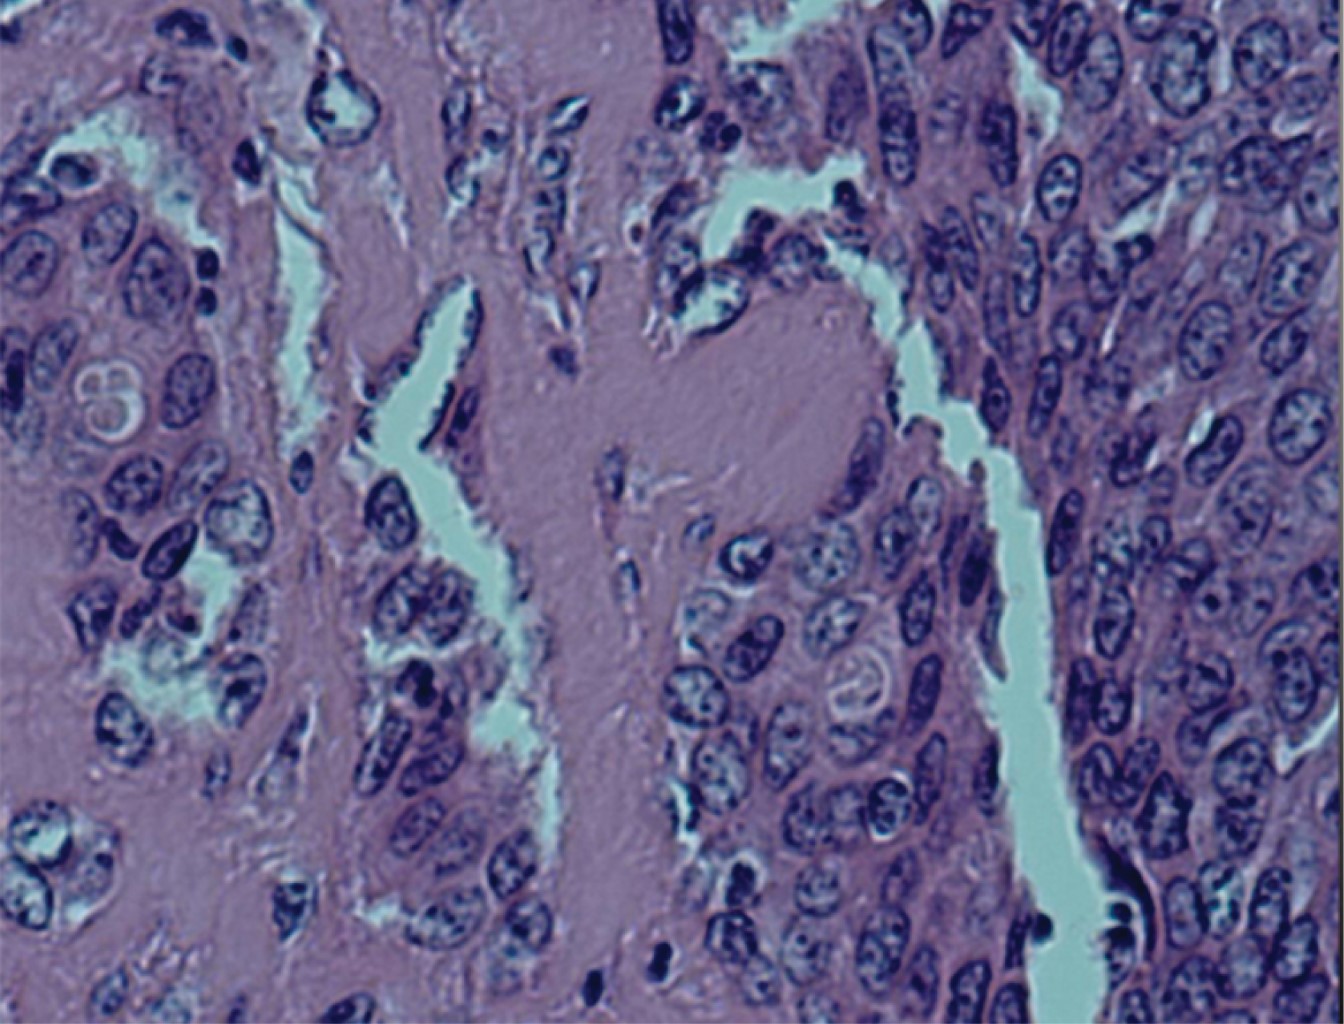

Basal cell adenocarcinoma of the minor salivary gland of the cheek

Salivary tumors can develop under the same histologic morphology in any of the glands. Of these, 80% occur in the parotid gland, 10 to 15% in the submaxillary gland and 5 to 10% in the sublingual and minor salivary glands. In major salivary gland tumors, approximately 80% are benign, but in minor salivary glands 35 to 80% are malignant, with clinical and histopathologic variations. The probability of a salivary tumor being malignant increases the smaller the size of the gland in which it is located. Minor salivary gland tumors (MSGTs) are rare, accounting for 10-15% of all salivary neoplasms. Despite their relatively low frequency, MSCTs constitute a heterogeneous group of neoplasms with a wide variety of histologic types.

Figure 1